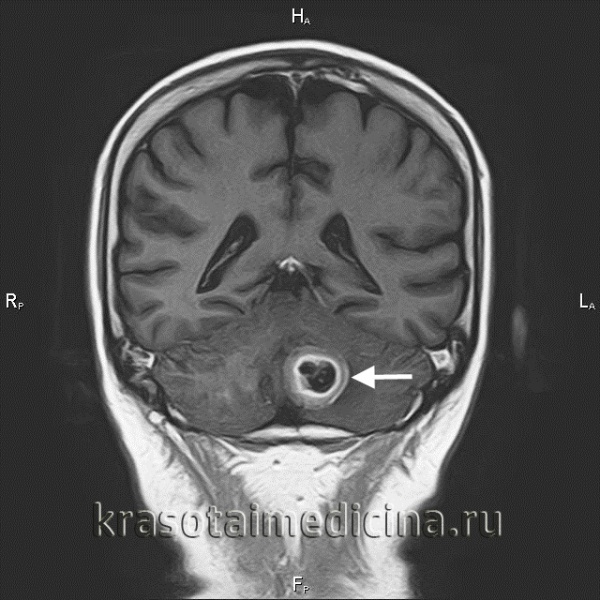

(а) МРТ, Т2-ВИ SPACE, аксиальный срез: у мужчины 57 лет со шванномой в области правого мостомозжечкового угла определяется гетерогенно гипоинтенсивное объемное образование, распространяющееся вплотную к яремному отверстию.

(б) Отмечается интенсивное контрастирование образования по типу мишени, что является признаком шванномы. Учитывая локализацию и распространение, опухоль может развиваться из ЧН IX, X, XI. Центральная область, не накапливающая контраст, соответствует участку гиперинтенсивного на Т2-ВИ (не представлены) сигнала, что часто наблюдается в областях Антони В с гипоцеллюлярностью и миксоидной стромой.